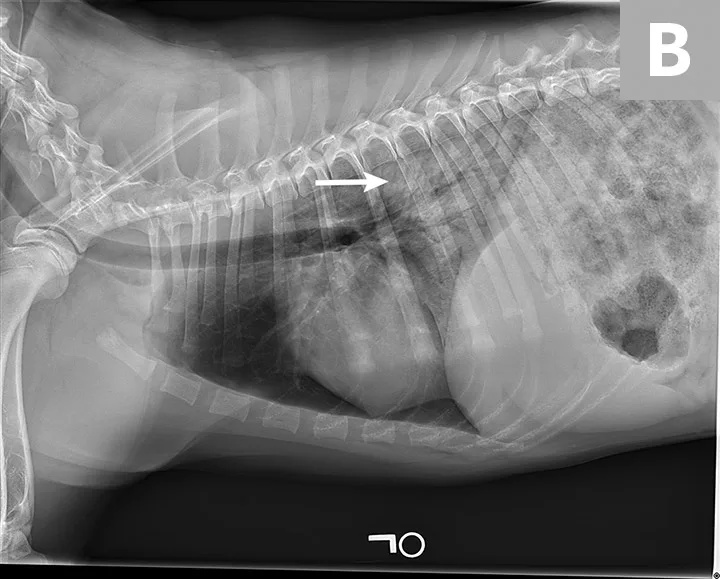

Blood pressure was decreased (85 mm Hg) on Doppler ultrasound. Oxygen saturation was initially 92% but increased to 98% with flow-by oxygen supplementation via mask (4 L/minute). Initial blood work showed mild hyperlactatemia (3.1 mmol/L; reference range, 0-2.5 mmol/L), packed cell volume of 54%, and total solids at 6.8 g/dL. Chest radiography was performed with oxygen supplementation and revealed a moderate to severe caudodorsal interstitial to alveolar lung pattern (Figures 1 and 2).

Radiographs showing caudodorsal alveolar pattern consistent with noncardiogenic pulmonary edema (arrows). Edema is caudodorsal and bilateral. The heart size is normal, and there is no elevation of the airways that would indicate left-sided heart enlargement. Sternal contact of the heart, which might suggest right-sided heart enlargement, is minimal.

The caudodorsal, bilateral, interstitial to alveolar pattern seen on radiographs is most consistent with noncardiogenic pulmonary edema (NCPE). Other differential diagnoses typically include cardiogenic edema or pneumonia. However, because Charlie was 6 months of age with a normal heart size and no murmurs or arrhythmias auscultated, cardiogenic edema was less likely. Expected pulmonary changes to the lungs are more diffuse with fungal or viral pneumonia or more discrete with bacterial pneumonia. NCPE was most likely in this patient because of the caudodorsal, bilaterally symmetric pattern and history of presumptive electrocution.